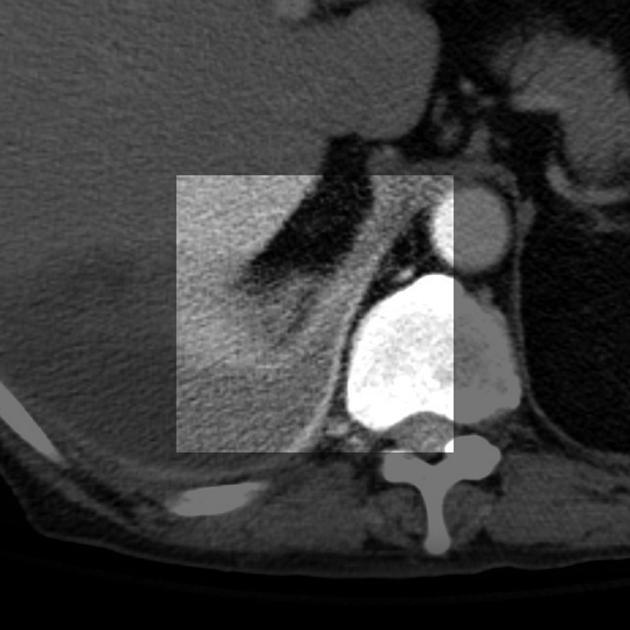

Split pleural sign?

Espessamento e realce da pleura visceral e parietal separadas por derrame exsudativo/empiema.

Empiema, evienciando o split pleural sign.